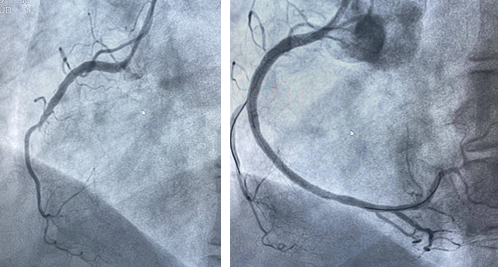

情况紧急,胸痛中心迅速响应,在与家属沟通并签署知情同意书的同时,同步办理住院手续,全程开通绿色通道,最快的速度把吕女士送入导管室接受急诊PCI治疗(经皮冠状动脉介入治疗)。在王宁夫主任医师指导下,徐鹏和钱宇峰副主任医师为她进行介入治疗,术中发现她的右侧冠状动脉近段完全闭塞,通过球囊扩张并植入支架,成功开通了堵塞的血管,恢复了心肌供血。

图说:左图术前右冠中段完全闭塞,右图术后右冠完全开通